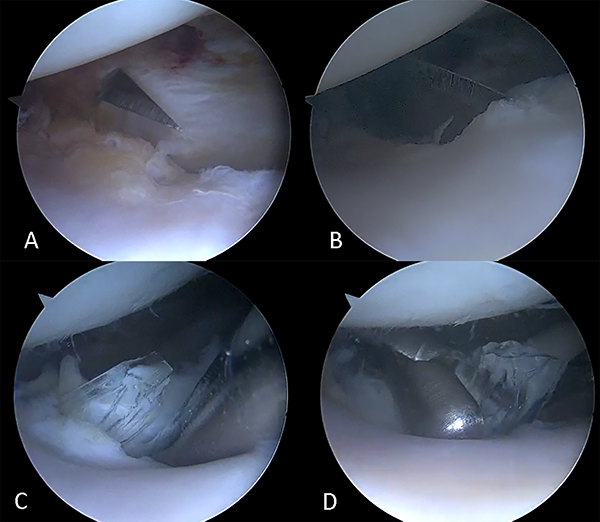

Bajo anestesia general y regional, por portales estándar anteromedial y anterolateral se exploró el compartimento medial sin lesión meniscal, pero con condrolisis generada por la impronta del vidrio a ese nivel (fig. 5A), en intercóndilo LCA y LCP sin particularidades. A nivel de compartimento lateral se evidenció lesión condral del cóndilo femoral y del platillo tibial como impronta de un cuerpo extraño (fig. 5B), menisco lateral sin lesión y de características normales (fig. 5C). Se ubicó un fragmento de vidrio de 4 mm en la región inframeniscal del tercio anterior del menisco lateral y se lo retiró (fig. 5D).

Figura 5. Visión artroscópica de rodilla derecha. A: Condrolisis en compartimento medial. B: Condrolisis de compartimento lateral. C: Menisco externo sin lesión. D: Exéresis de vidrio ubicado inframeniscal externo.